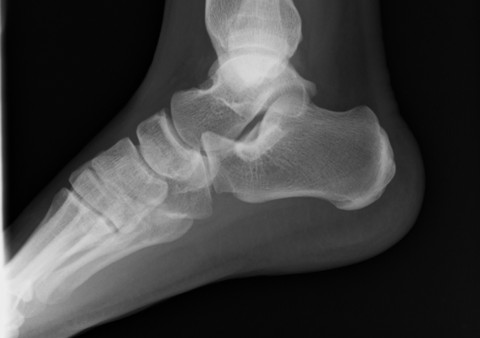

一般的には「ふくらはぎが硬い」と言われますが、本質は足首(距腿関節)の可動制限。

足首がスムーズに曲がらないと歩行時の衝撃が逃げ場を失い、足底筋膜に集中します。